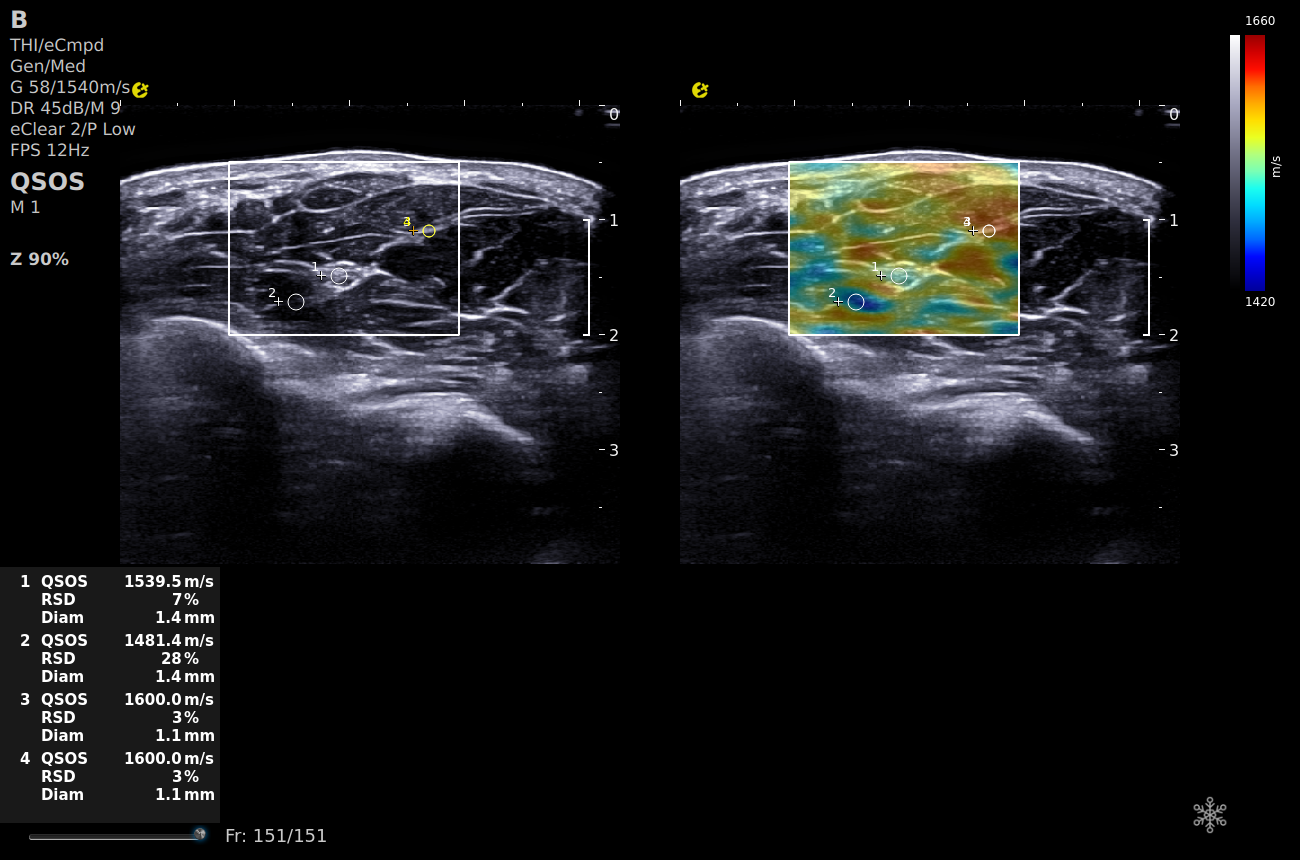

QSOS(speed of sound)声速定量成像